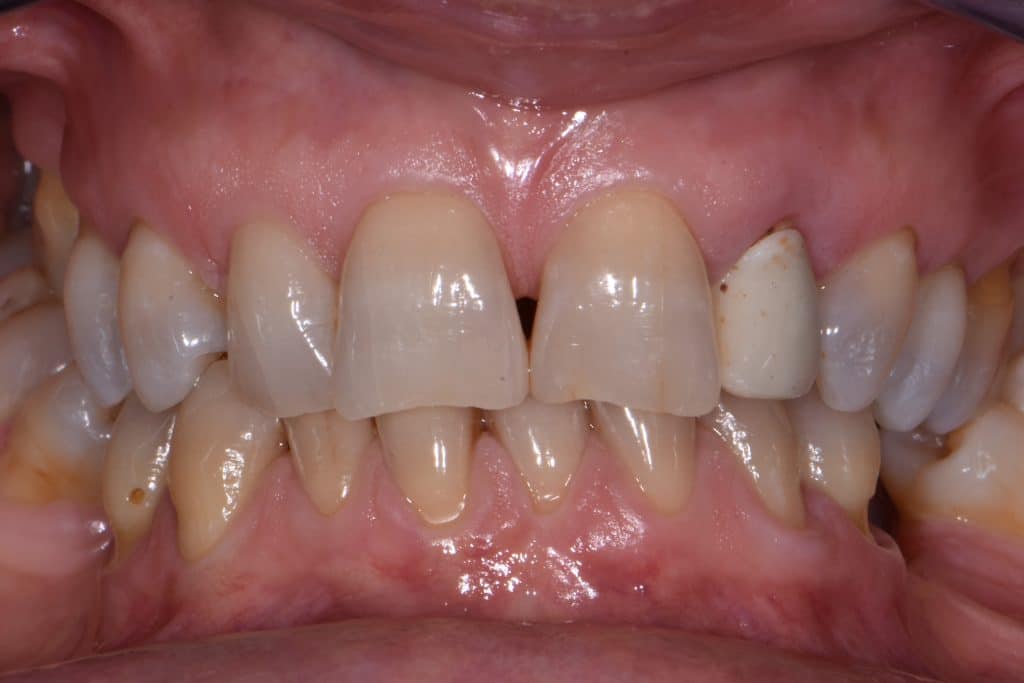

La pz N.G. di anni 52 (ASA 1) viene visitata nel mese di settembre 2017 per la mobilità ed inestetismo dell’elemento protesico 22, (foto iniziali sequenza 1) si evidenzia una frattura parziale della radice, si decide per l’estrazione ( foto sequenza 2) e sostituzione dell’elemento con un restauro implanto-protesico. Purtroppo la scarsa quota ossea apicale all’alveolo post-estrattivo (foto 2 rx) e l’alta valenza estetica dell’elemento ci rende cauti e si programma una socket preservation post estrattiva con l’ausilio delle membrane di prf (foto prf e socket sequenza 3 e 4). Durente i 5 mesi di guarigione la pz porta una protesi parziale mobile (foto 5,2) , a guarigione del sito post estrattivo si evidenzia una buona conservazione dei volumi osseo-gengivali,(foto guarigione sequenza 6) se pur presente una recessione distale all’elemnto 21.Nel mese di febbraio 2018 si procede all’inserimento di un impianto max-stability 3,75x12mm disegnando un lembo anticipato palatino per consentire un aumento dei tessuti vestibolari suturando con tecnica rool flap e trasformando l’elemento parziale mobile in una corona singola a carico immediato sul moncone temporameo applicando i concetti protesici bopt , (foto impianto moncone protesi provvisoria sequenza foto 7-8-9). Durante il periodo di maturazione dei tessuti molli vengono apportate opportune modifiche ai profili del provvisorio al fine di dare maggior spazio al tessuto gengivale, ( fotosequenza 10).Dopo circa 2 mesi dal protesizzazione provvisoria si è proceduto alla realizzazione del manufatto protesico con tecnica chair side sirona con l’ausilio del t-base (foto sequenza 11-12-13), realizzando in una sola seduta una corona in disilicato, ottenendo un risultato più che soddisfacente (Foto 14). Nel controllo a 3 mesi dal carico definitivo si apprezza la perfetta conservazione dei livelli ossei e gengivali. (foto sequenza 15).concludo con un follow up a 18 . Tengo a sottolineare che un caso come questo è stato conducibile con buoni risultati solo grazie alla piena fiducia della pz e alla sua massima motivazione e collaborazione. Ad oggi la pz sorride soddisfatta del risultato. E questo rappresenta la massima ricompensa di chi dedica tutto se stesso alla professione.